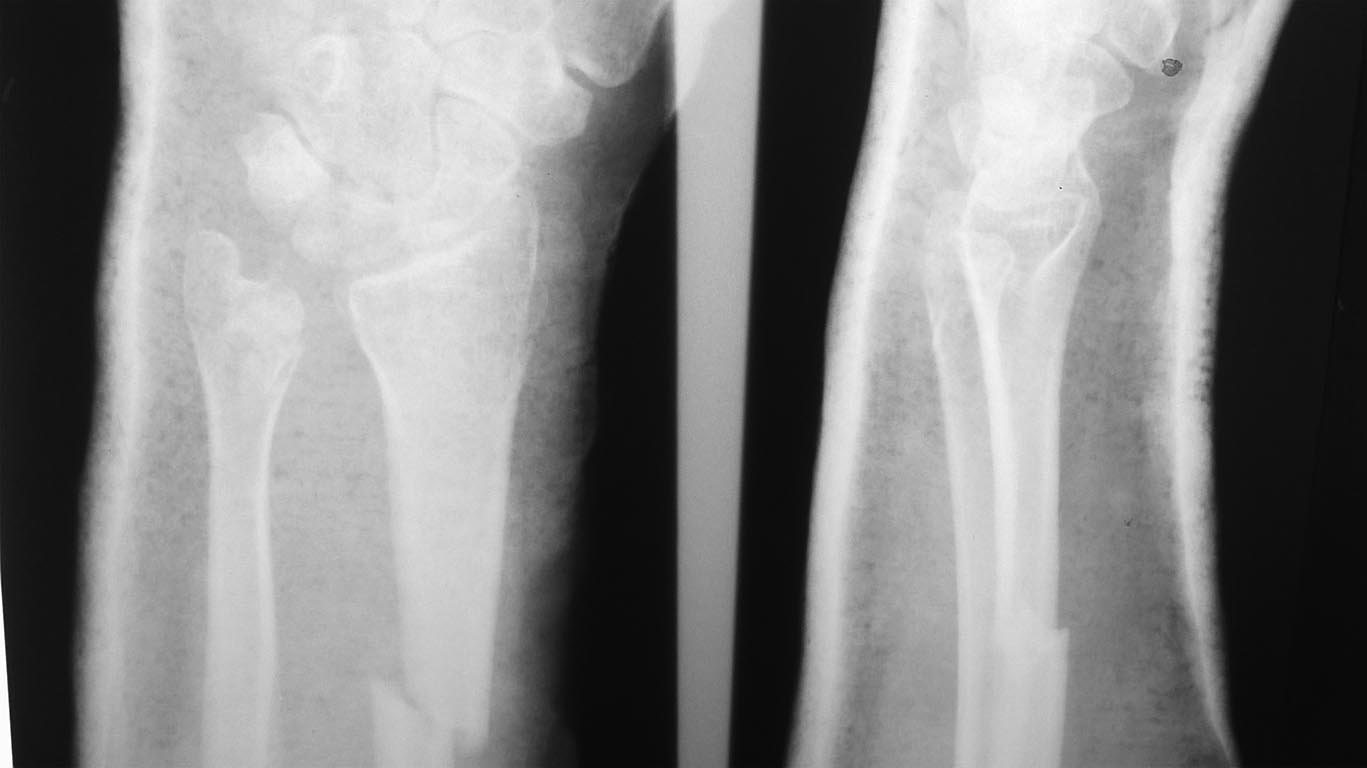

перелом Galeazzi

К нам поступила женщина с закрытым переломом диафиза лучевой кости и переломом головки локтевой кости с повреждением дистального радиоульнарного сочленения.

В плане открытый накостный остеосинтез лучевой кости. Нужен совет по поводу вмешательства на локтевой кости,если на интраоперационных снимках подвывиха головки локтевой кости не будет